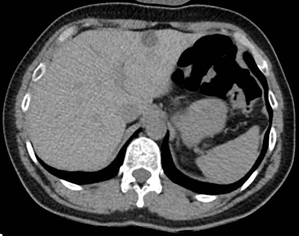

Subsequently, the patient reported a similar episode a year ago while riding a bike, which resulted in a wrist fracture. However, it was not studied by then. During his hospitalization the patient presented repeated episodes of hypoglycemia, so studies were expanded, a lipid profile, thyroid function, and plasma cortisol were performed, all of which were normal, and possible infection was ruled out. It was evaluated in conjunction with the endocrinology service, who indicated imaging studies and a 72 hours fasting test because of insulinoma suspicion. Computed tomography (CT) with abdominal contrast and magnetic resonance cholangiopancreatography (MRCP) were performed, showing a cystic image in the liver without other significant anomalies (Figures 1 and 2). A 72-hour carbohydrate fasting test was performed, which ended after 14 hours due to symptoms of hypoglycemia and fingerstick blood glucose of 36 mg/dL (2 mmol/L). Laboratory tests were taken immediately, confirming venous blood glucose of 35 mg/dL (1.94 mmol/L) and insulin of 46.7 uIU/mL (high, reference range 2.6 - 25 uIU/ml). Then dextrose intravenous was administered and the symptoms resolved. Unfortunately, in our hospital there is no availability to measure C-peptide, beta-hydroxybutyrate, proinsulin levels and anti-insulin antibodies.

Figure 2 MRCP shows pancreas with preserved and signal, without evidence of nodular lesions.